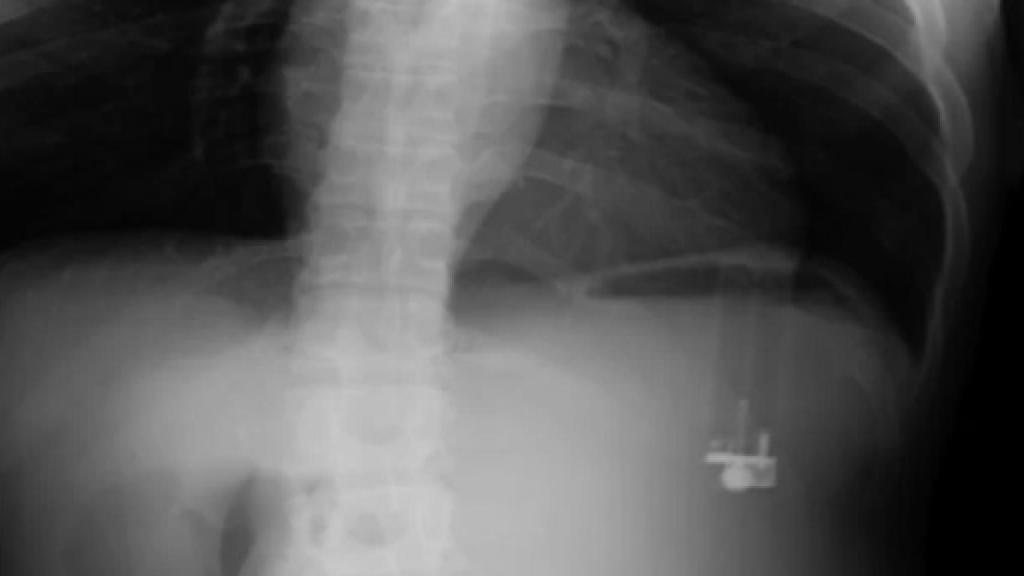

Radiografía en la que se aprecia el encendedor dentro del estómago.

Durante su estancia en urgencias, los médicos le realizaron análisis de sangre y orina cuyos resultados se encontraban dentro de la normalidad. Sin embargo, tras realizarle una radiografía del abdomen, se logró vislumbrar el problema: un cuerpo extraño de características similares a un mechero se encontraba dentro de su estómago.